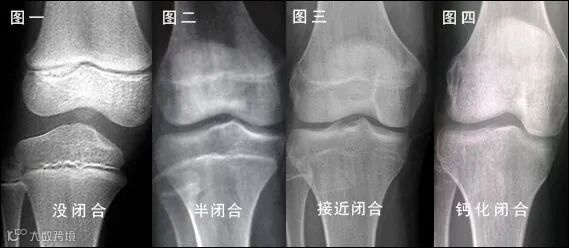

身高生长停止的标志是骨骺和骨干

完全融合成长板消失

男童约为骨龄16岁女童约为骨龄14岁

一图读懂骨骺闭合